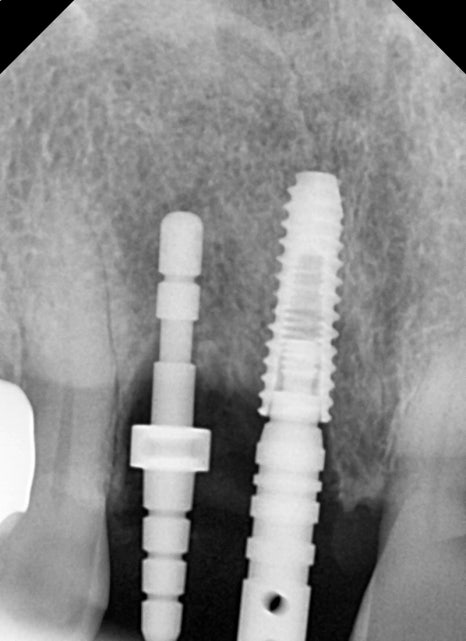

임플란트 식립

발치와 동시에 임플란트 수술을 먼저 진행했습니다

특별히 어려울 것 없이 식립 방향을 체크하며

치주염에 의해 부족한 뼈는 치조골 이식이라는 뼈이식을 통해

부족한 볼륨을 회복시켜줬습니다.